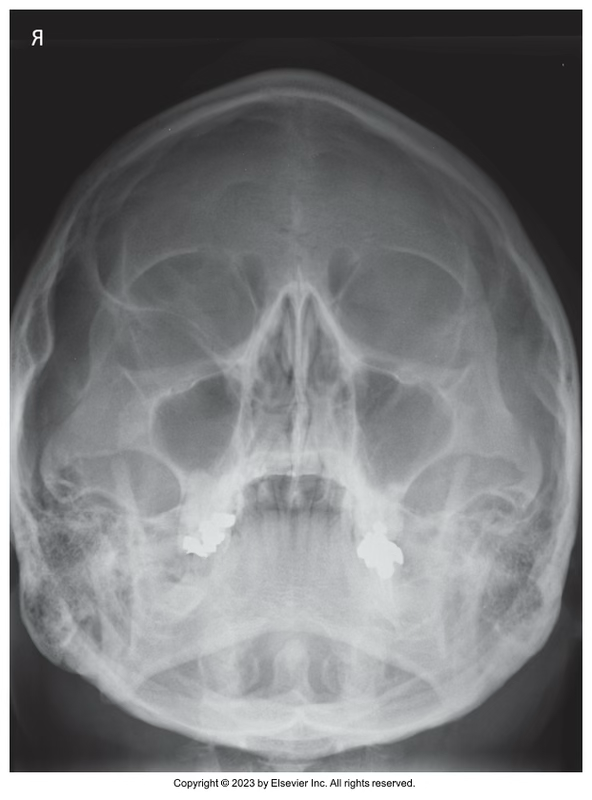

What view is this?

Waters